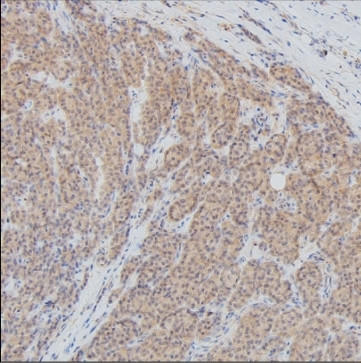

Product information "Anti-GAPDH"

Protein function: Has both glyceraldehyde-3-phosphate dehydrogenase and nitrosylase activities, thereby playing a role in glycolysis and nuclear functions, respectively. Participates in nuclear events including transcription, RNA transport, DNA replication and apoptosis. Nuclear functions are probably due to the nitrosylase activity that mediates cysteine S-nitrosylation of nuclear target proteins such as SIRT1, HDAC2 and PRKDC. Modulates the organization and assembly of the cytoskeleton. Facilitates the CHP1-dependent microtubule and membrane associations through its ability to stimulate the binding of CHP1 to microtubules. Glyceraldehyde-3-phosphate dehydrogenase is a key enzyme in glycolysis that catalyzes the first step of the pathway by converting D-glyceraldehyde 3-phosphate (G3P) into 3- phospho-D-glyceroyl phosphate. Component of the GAIT (gamma interferon- activated inhibitor of translation) complex which mediates interferon- gamma-induced transcript-selective translation inhibition in inflammation processes. Upon interferon-gamma treatment assembles into the GAIT complex which binds to stem loop-containing GAIT elements in the 3'-UTR of diverse inflammatory mRNAs (such as ceruplasmin) and suppresses their translation. [The UniProt Consortium]

| Keywords: | Anti-Glyceraldehyde-3-phosphate dehydrogenase, Anti-GAPDH, Anti-Peptidyl-cysteine S-nitrosylase GAPDH, GAPDH Antibody |

| Supplier: | Absea |

| Supplier-Nr: | KC-2172 |

| Antibody Type: | Monoclonal |

| Clone: | KT186 |

| Conjugate: | No |

| Host: | Mouse |

| Species reactivity: | human, rat, mouse |

| Immunogen: | Synthetic peptide within the region aa 180-230 of human GAPDH |